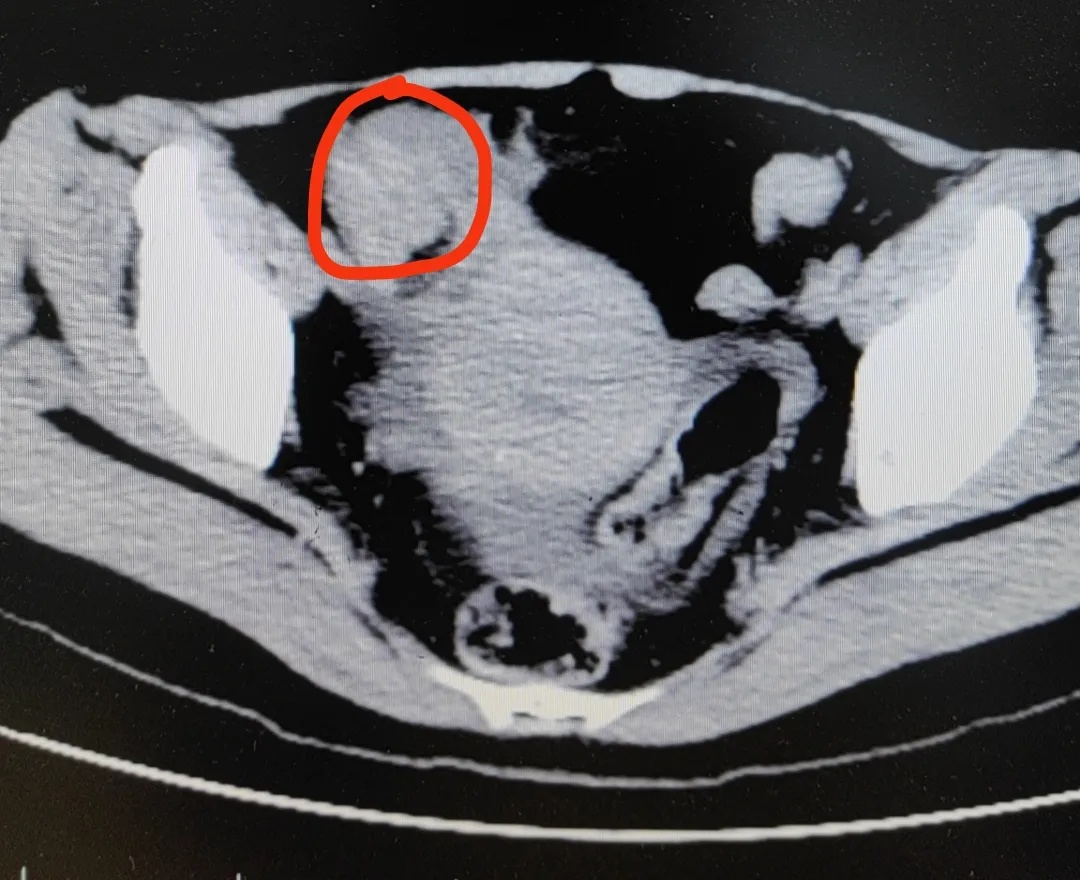

医生高度怀疑,冯女士发生了绞窄性肠梗阻。最后手术从她的肠子里切出一堆“石头”,最大的直径有4公分,确诊“柿石症”。